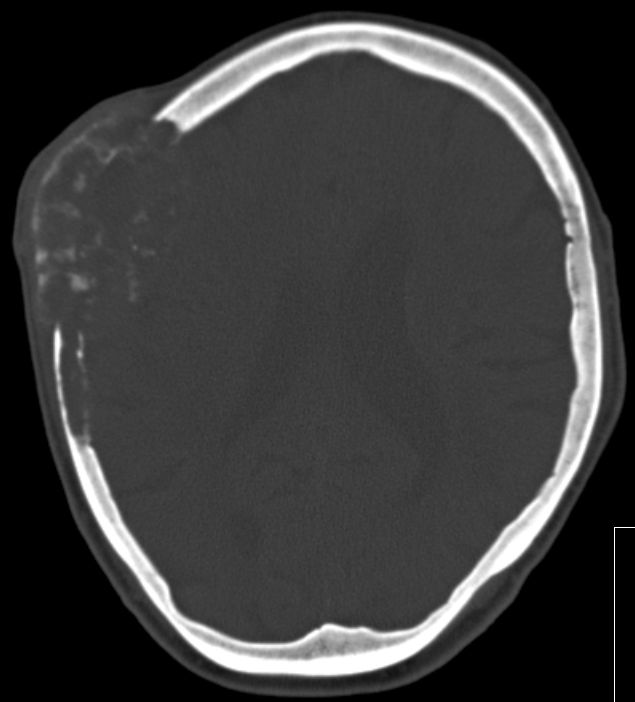

| Schädel | 86-jährige Frau mit primär ossär metastasiertem Adenokarzinom des linken Oberlappens.

Monate nach Diagnose klagte die Patientin über eine schmerzlose Schwellung des Kopfes rechts. Das Nativ-CT zeigt eine Metastase des Schädelknochens.![]() |

Im Knochenfenster deutlich größere Zerstörung sichtbar.![]() |